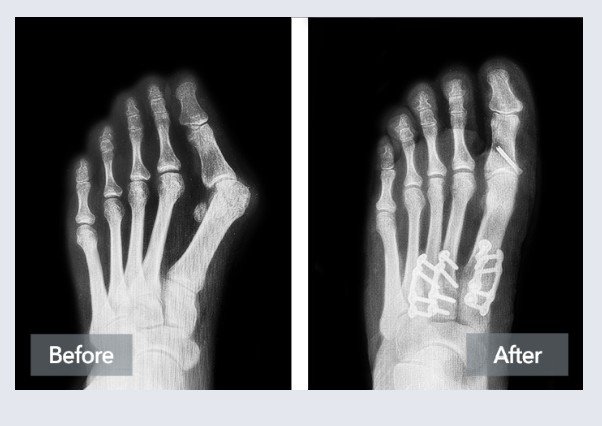

A bunion, or hallux valgus, is a three-dimensional deformity involving medial deviation of the first metatarsal, lateral deviation and pronation of the hallux, and instability at the first tarsometatarsal (TMT) joint.⁵ The triplanar nature explains why purely two-dimensional corrections often relapse — true correction must address all planes and the apex of deformity.⁵ ⁹

Surgical Options: Why I Favor Lapidus-Based Procedures

The Lapidus procedure fuses the first TMT joint (the joint BEHIND where you see the bunion sticking out), correcting deformity at its origin and in all three planes.⁵ ⁹ This is especially valuable for:

Modern fixation allows protected early weight bearing, which I’ve incorporated into my protocol — most patients walk in a boot the same day.¹² ¹³ ¹⁴

• Instrumented triplanar correction at the TMT joint with biplanar plating.⁹ ¹⁰ ¹¹

• Reported fusion rates ~99% with low recurrence.¹¹

• Early boot walking is often possible in 7–10 days in studies; in my protocol, it is usually same day for healthy adults.